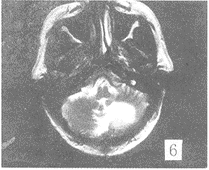

在FLAIR序列所发现81个病灶中,FSET2序列能显示的有66个,FSET2序列对病变显示率 为81.4%。FSET2序列未显示的15个病灶均位于侧脑室下、脑室旁及脑灰质区(图1,2) 。位 于脑室下的病灶,T2像未能显示。而位于基底节区,脑白质区的病灶,FLAIR及FSET2序列都 能显示。T2加权像上,所有病灶均为高信号。但在FLAIR序列,有2个病灶为低信号,1例出 血,出血灶的低信号部份T2像未能显示。另1例是T2加权像没能显示的血管畸形远端侧枝 循环(图3,4),此例为左侧颈内动脉畸形,左顶叶侧枝循环,T2像未能显示。在T2像上没能 显示而FLAIR像显示的15个病灶中,有10例为脑梗塞、脱髓鞘病变和皮层下动脉硬化性脑病 , 病灶位于脑灰质,受脑脊液影响T2像未能显示。2例为转移瘤(图5,6),肿瘤位于脑灰质,T 2像仅见水肿影。2例为脑炎、脑膜炎(图7,8),在T2像上病灶完全被脑沟中的脑脊液所掩盖 。

图5 FLAIR像示左小脑半球转移瘤,肿瘤与水肿界限清楚。FSET2 像(图6)肿瘤与水肿界限不清